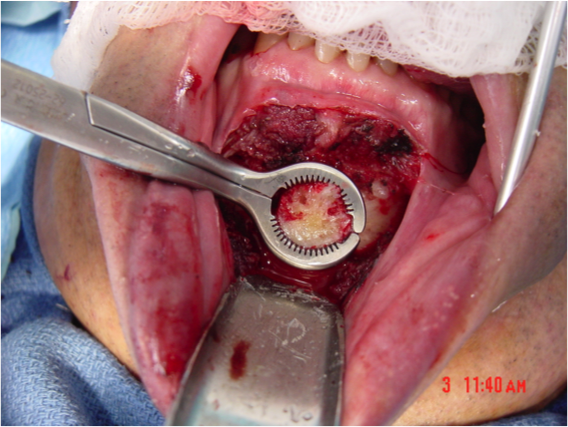

This procedure places tension on the tongue, limiting the posterior from shifting during sleep. The procedure starts with a small incision made inside the lower lip. Then, the surgeon moves away all the soft tissue to expose the lower jaw. Small rectangular cuts are then made in the lower jaw directly in front of the lower front teeth. This area attached to the genioglossus muscle is then moved forward and turned slightly. To hold this bone fragment in place, the surgeon puts in a titanium screw to immobilize it.

The photos on this website are from real surgeries performed by Dr. Ulloa. Due to the

graphic nature of the images and content, viewer discretion is advised.